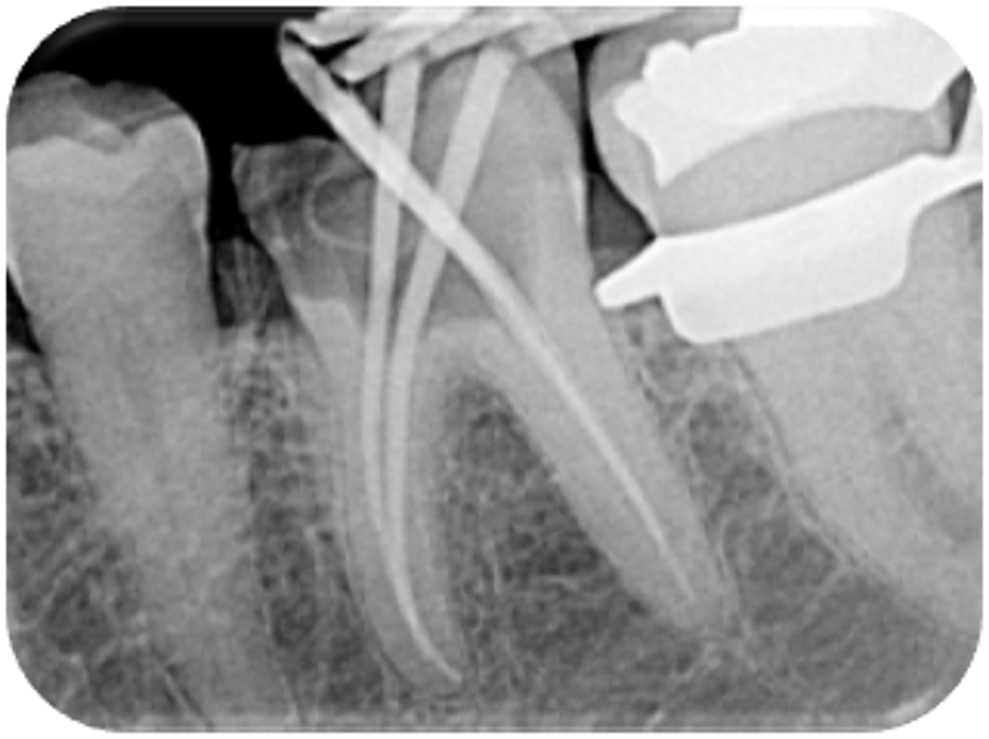

Fig. 5: Master point radiograph.

After apical gauging, matching Hyflex EDM gutta-percha points were placed, and a master point long-cone periapical radiograph of tooth #36 was performed to assess the apical extent of the master gutta-percha points (Fig. 5). Reporting showed a potential obturation to within 2 mm of the radiographic apex.